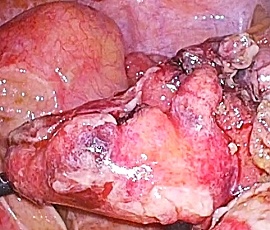

右下腹部痛にて受診。精査の結果、急性虫垂炎、汎発性腹膜炎と診断。手術(腹腔鏡下回盲部切除術、腹腔内ドレナージ術)を施行した。

手術画像